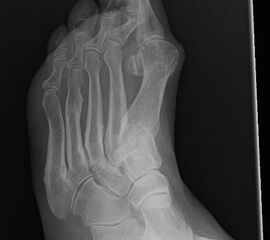

Die Überbelastung des Metatarsale II und III im distalen Bereich äußert sich in Druckschmerzen und Schwielenbildung plantar unter den Metatarsale II und III Köpfen (Abb. 1). Auch degenerative Veränderungen der plantaren Kapsel und der plantaren Platte der Metatarsophalangealgelenke treten auf, was zu einer Insuffizienz der Grundgelenke mit Subluxation oder Luxation der Kleinzehen führt (Abb. 2 und 3).

Die Überbelastung im Schaftbereich wird selten von den Patienten wahrgenommen. Manchmal findet sich vor allem am Os metatarsale II proximal eine Stressfraktur. Adaptiert sich der Knochen, kann im Röntgenbild häufig eine Kortikalisverdickung im Bereich der Metatarsale II und III Schäfte als Ausdruck einer vermehrten Lasteinleitung beobachtet werden (Abb. 4).